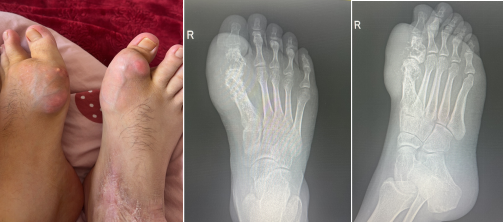

患者张先生,28岁,痛风病史5余年,因长期控制不佳,双足第一跖趾关节反复肿痛、逐渐变形,右足第一跖趾关节最终发展为关节软骨全层剥脱、大面积骨缺损、外翻畸形、关节半脱位。行走剧痛、无法穿鞋、夜间痛醒,保守治疗与传统手术均难以解决骨缺损与畸形问题,常规成品假体无法适配其严重破坏的骨骼形态。

骨伤科二病区团队为其制定一期行双足针刀镜微创手术彻底清理痛风石:

一期微创手术清理术后